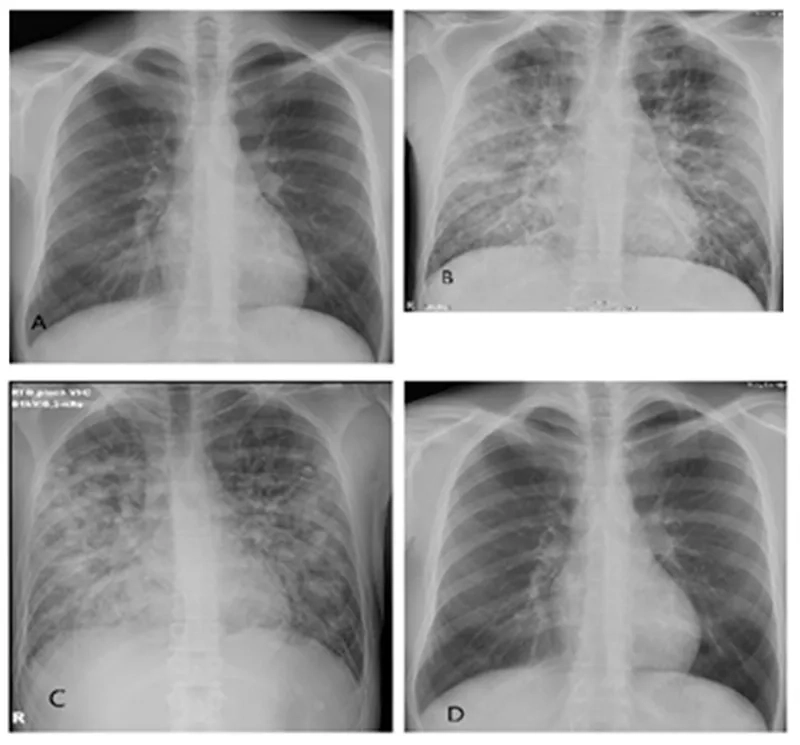

Image Gallery Hantavirus Pulmonary Syndrome

• After a few days, late-stage symptoms like coughing and shortness of breath appear as the lungs fill with fluid.